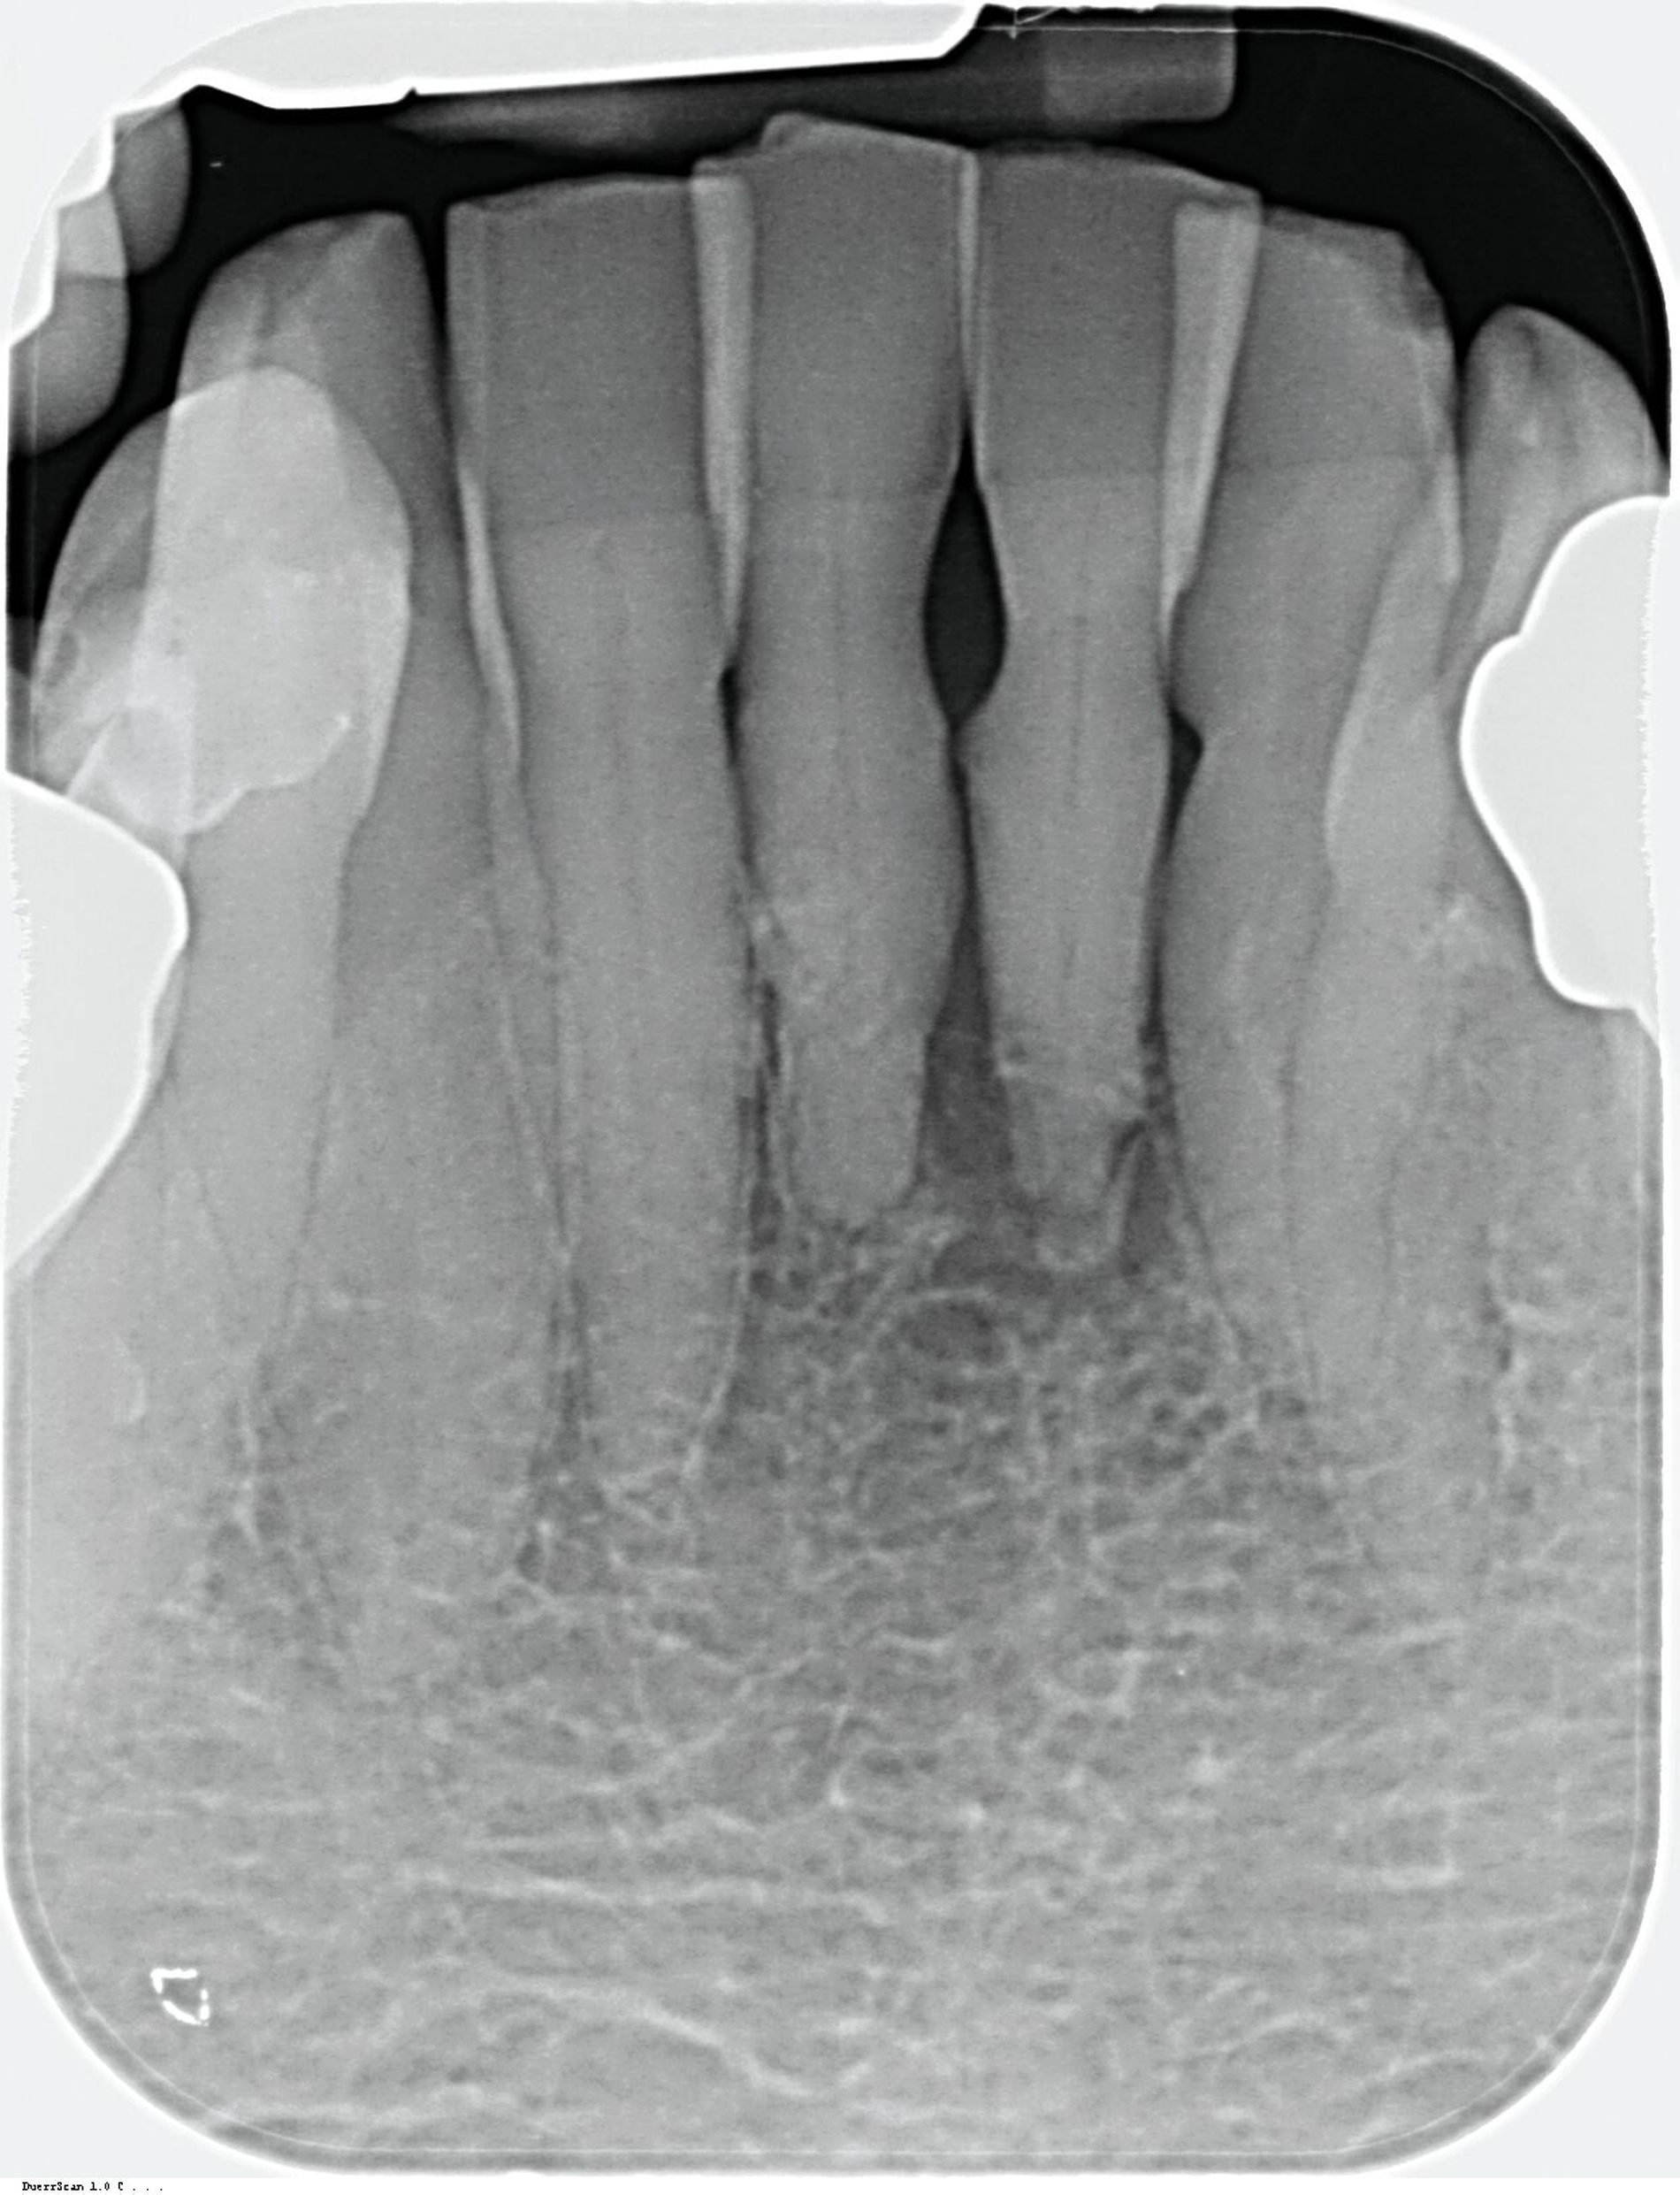

Obwohl die unterstützende Parodontitistherapie (UPT) vier Jahre unterbrochen war, konnte bis auf einen Grad III gelockerten Zahn 31 und eine Grad I–II gelockerte, restliche Unterkieferfrontbezahnung ein gut erhaltenes Gebiss festgestellt werden. Dies ist auch darauf zurückzuführen, dass die Patientin – trotz ihres fortgeschrittenen Alters – die häusliche Mundhygiene stets sehr gründlich betrieb, wie auch aus früheren Akteneinträgen ersichtlich wurde (Abbildung 4).

Da anhand eines Zahnfilms festgestellt worden war, dass der Zahn 31 – vermutlich aufgrund einer Paro-Endo-Läsion – eine apikale Aufhellung zeigte, war bereits die Extraktion mit anschließender Umarbeitung und adhäsiver Wiedereingliederung des extrahierten Zahnes als Option angesprochen worden. Kurz vor dem vereinbarten Eingriff meldete sich die Patientin telefonisch, um sich zu erkundigen, ob sie den Termin denn überhaupt noch benötige, da der betroffene, gelockerte Zahn 31 in der Unterkieferfront beim Essen von selbst herausgefallen sei und sie ihn bereits entsorgt habe. Schmerzen, eine Schwellung oder Nachblutungen verneinte die Patientin. Sie wurde gebeten, den vereinbarten Termin am Folgetag dennoch wahrzunehmen, mindestens zur Kontrolle der Wunde, gegebenenfalls zur Planung der Weiterversorgung (Abbildungen 5 und 6).